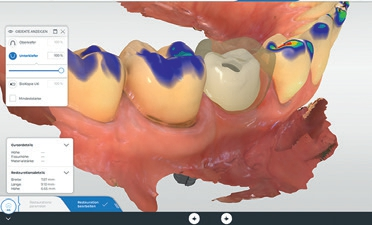

Zur optimalen Behandlungsplanung wurde neben dem DVT ein intraoraler Scan mit der CEREC Omnicam durchgeführt. Die vorhandenen Daten wurden sodann im Implantatplanungsprogramm (Galileos Implant, Dentsply Sirona) für die prothetische Planung sowie für das Design einer Bohrschablone mittels der CERECSoftware vorgenommen und zusammengeführt. Die Fertigung der Bohrschablone erfolgte binnen 45 Minuten direkt in der Praxis mit der Schleifeinheit CEREC MC XL Premium Package. Anschließend wurde die Titanhülse für die geführte Insertion eingeklebt (Abb. 4 bis 6).